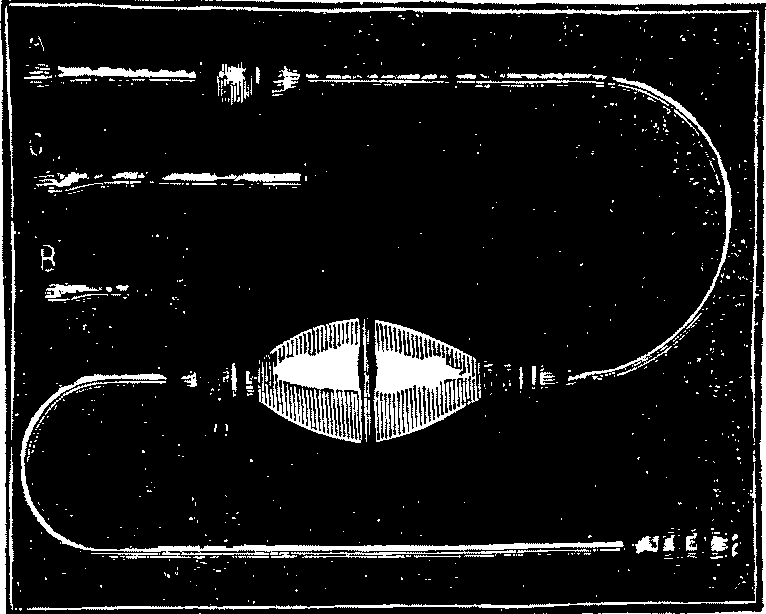

How to Use Vaginal Injections. We usually recommend the Fountain Syringe illustrated in Fig. 6, as the most convenient instrument for administering vaginal injections. The fountains supplied by us are of soft rubber, and have extra nozzles, with which to make rectal, nasal or ear irrigations. There is also a large, long nozzle for vaginal injections.

Fig. 7. SOFT RUBBER-BULB SYRINGE

It is channeled so is to permit the free clearing [pg 706]away of the secretions as the Douche is employed. The Fountain Syringe can he used without assistance, the flow of fluid is gradual, and with a force that can be varied, by raising or lowering the reservoir, yet is never so great as to be liable to produce injurious effects.

The syringes usually sold with small nozzles or pipes are of little or no value for vaginal injections. In many instances so small a tube will pass readily into the canal of the uterus, and hence there has frequently resulted an injection of a portion of the fluid into the uterus itself, producing severe pain. It is important, therefore, in using the Vaginal Douche to employ only a large tube that has grooves in its surface for the free clearing away of the fluid as it runs from the fountain.

Where it is desired to obtain relief from a congested, inflamed or sensitive and irritable state of the mucous surface, the employment of a large quantity of water as hot as it can be borne, is of the greatest remedial value. It rapidly diminishes the size of the blood vessels, and aids in bringing about a normal circulation in the parts.

As a rule, in taking the Douche with the Fountain Syringe the rubber bag is filled, and suspended from a nail or hook at a height of from two to five feet above the patient, and the fluid passes through the tube by force of gravity, thus requiring no muscular exercise. The force of the stream depends upon the height of the fountain above the outlet nozzle. It is only necessary that the patient should assume a comfortable position where the fluid which comes from the vaginal canal can flow into a water closet, or any convenient vessel.

After a thorough cleansing of the vaginal surfaces of mucus, by means of the warm or hot water, it is sometimes advisable to inject remedial fluids. These injections may readily be made with the fountain or bulb syringe, introducing not less than from two to four ounces. This may be retained sufficiently long to exert its remedial effects upon the mucous surface, which usually takes from five to eight minutes. The hips should be elevated, and the nozzle of the syringe surrounded by a napkin or other similar material, upon which moderate compression can be made so as to retain the fluid in the vagina for the necessary period.

To those who are unable readily to obtain the Fountain Syringe above recommended we can send by mail, post-paid, one of these instruments on receipt of $2.00.

A Soft Rubber-bulb, or Pump Syringe (illustrated in Fig. 7), not so good for making vaginal injections, can be sent by us, post-paid, for from 75cts. to $1.50, the price varying with the quality and size.